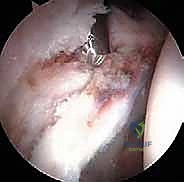

الخطوة 3: الاستكشاف بكاميرا 4K

يتم إدخال منظار مزود بكاميرا عالية الدقة (4K) وإضاءة قوية. تُعرض الصورة مكبرة على شاشة أمام الجراح، مما يسمح له برؤية أدق تفاصيل الغضروف والشفا الحقي بوضوح يفوق الرؤية بالعين المجردة.

الخطوة 5: إصلاح الشفا الحقي (Labral Repair)

إذا كان الشفا الحقي ممزقاً (وهو أمر شائع جداً)، لا يتم استئصاله، بل يحرص الدكتور هطيف على إصلاحه للحفاظ على وظيفة المفصل. يتم ذلك باستخدام "خطاطيف خياطة" (Suture Anchors) صغيرة جداً تُزرع في العظم وتُستخدم لربط وخياطة الشفا وإعادته لمكانه الطبيعي.